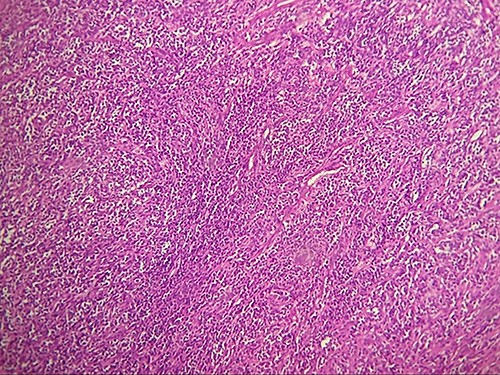

Macroscopically, the tumor was whitish, fleshy, firm, with a polylobed surface and harboring foci of necrosis. Histological examination showed densely cellular spindle cell proliferation without evidence of differentiation, with focal nuclear pleomorphism and few foci of tumor necrosis (<50%). Mitotic activity was high, estimated at 13 mitoses/10 fields at high power. (Figs 2–4) An exhaustive immunohistochemical study was necessary to classify this tumor (Cytokeratin AE1/AE3, Melan A, Epithelial Membrane Antigen (EMA), PS100, Smooth Muscle Actin (SMA), H-Caldesmone, Desmin, Myogenin, CD34, CD31, Chromogranin, Synaptophysin, CD56, P63, Beta-Catenin, STAT6 and SOX10). Tumor cells expressed SOX10 intensely and diffusely (Fig. 5), and PS100 focal (Fig. 6). The other markers were not expressed and the Ki 67 proliferation index was estimated at 60%.

HE section showing tumor cells pleomorphisme and mitotic figures (blue arrow) (x40).